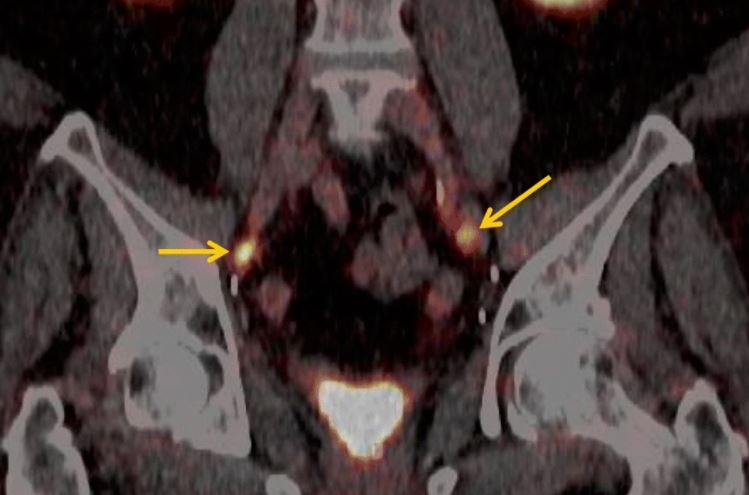

Áttörést hozhat a Pozitron-Diagnosztika Központ több százmillió forintos fejlesztése a prosztatarákkal diagnosztizáltak életében; az innovatív magyar egészségügyi cég által kifejlesztett nyomjelző anyag ugyanis a betegeknél az áttéteket minden eddigi módszernél pontosabban mutatja ki – ismertette Szakáll Szabolcs nukleáris medicina szakorvos, a Pozitron-Diagnosztika Központ orvos igazgatója az MTI-nek.

Az orvos igazgató elmondta, hogy a cég által kifejlesztett, speciális nyomjelzőt a központ saját laboratóriumában, saját részecskegyorsítójával állítja elő. Az egészségügyi fejlesztés révén a régióban elsőként Magyarországon nyílt lehetőség a nagy pontosságú PSMA-specifikus nyomjelző anyag alkalmazására a prosztatadaganatos betegek kivizsgálásában.

Szakáll Szabolcs felhívta a figyelmet arra, hogy a statisztikák szerint a prosztatarák Magyarországon a férfiak második leggyakrabban diagnosztizált daganata, mely az ötödik vezető halálok, az öregedő európai társadalmakra általában jellemzően. Évente 5-6000 új prosztatarákos megbetegedést diagnosztizálnak, a radikális műtéten átesettek egyharmadánál azonban a sebészi- vagy sugárterápiát követően kiújul a betegség, a fel nem fedezett áttétek miatt. A PSMA PET/CT-vizsgálatok elsődleges célja az ilyen kiújulások felderítése, kimutatása.